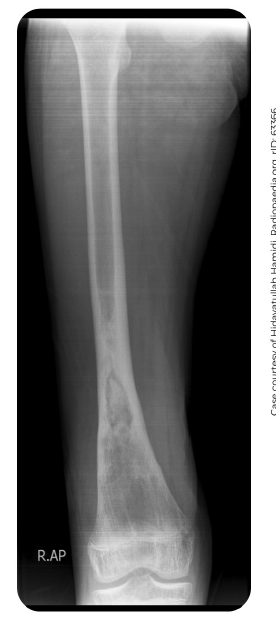

Osteomielite aguda

Epidemiologia, principal bactéria e tempo

RX com reação periosteal - 10 a 12 dias após

Cintilografia com aumento da captação em todas as fases

Osteomielite crônica

Geral

· Normalmente, resulta de uma osteomielite aguda não tratada

· >3 semanas

· Sequestro ósseo + fistulas

- ATB não chega pois ocorre formação de biofilme

· Tíbia é o osso mais afetado

. TC e útil para identificar um sequestro ou destruição da placa óssea subcondral e pode ajudar a determinar a extensão do envolvimento medular.